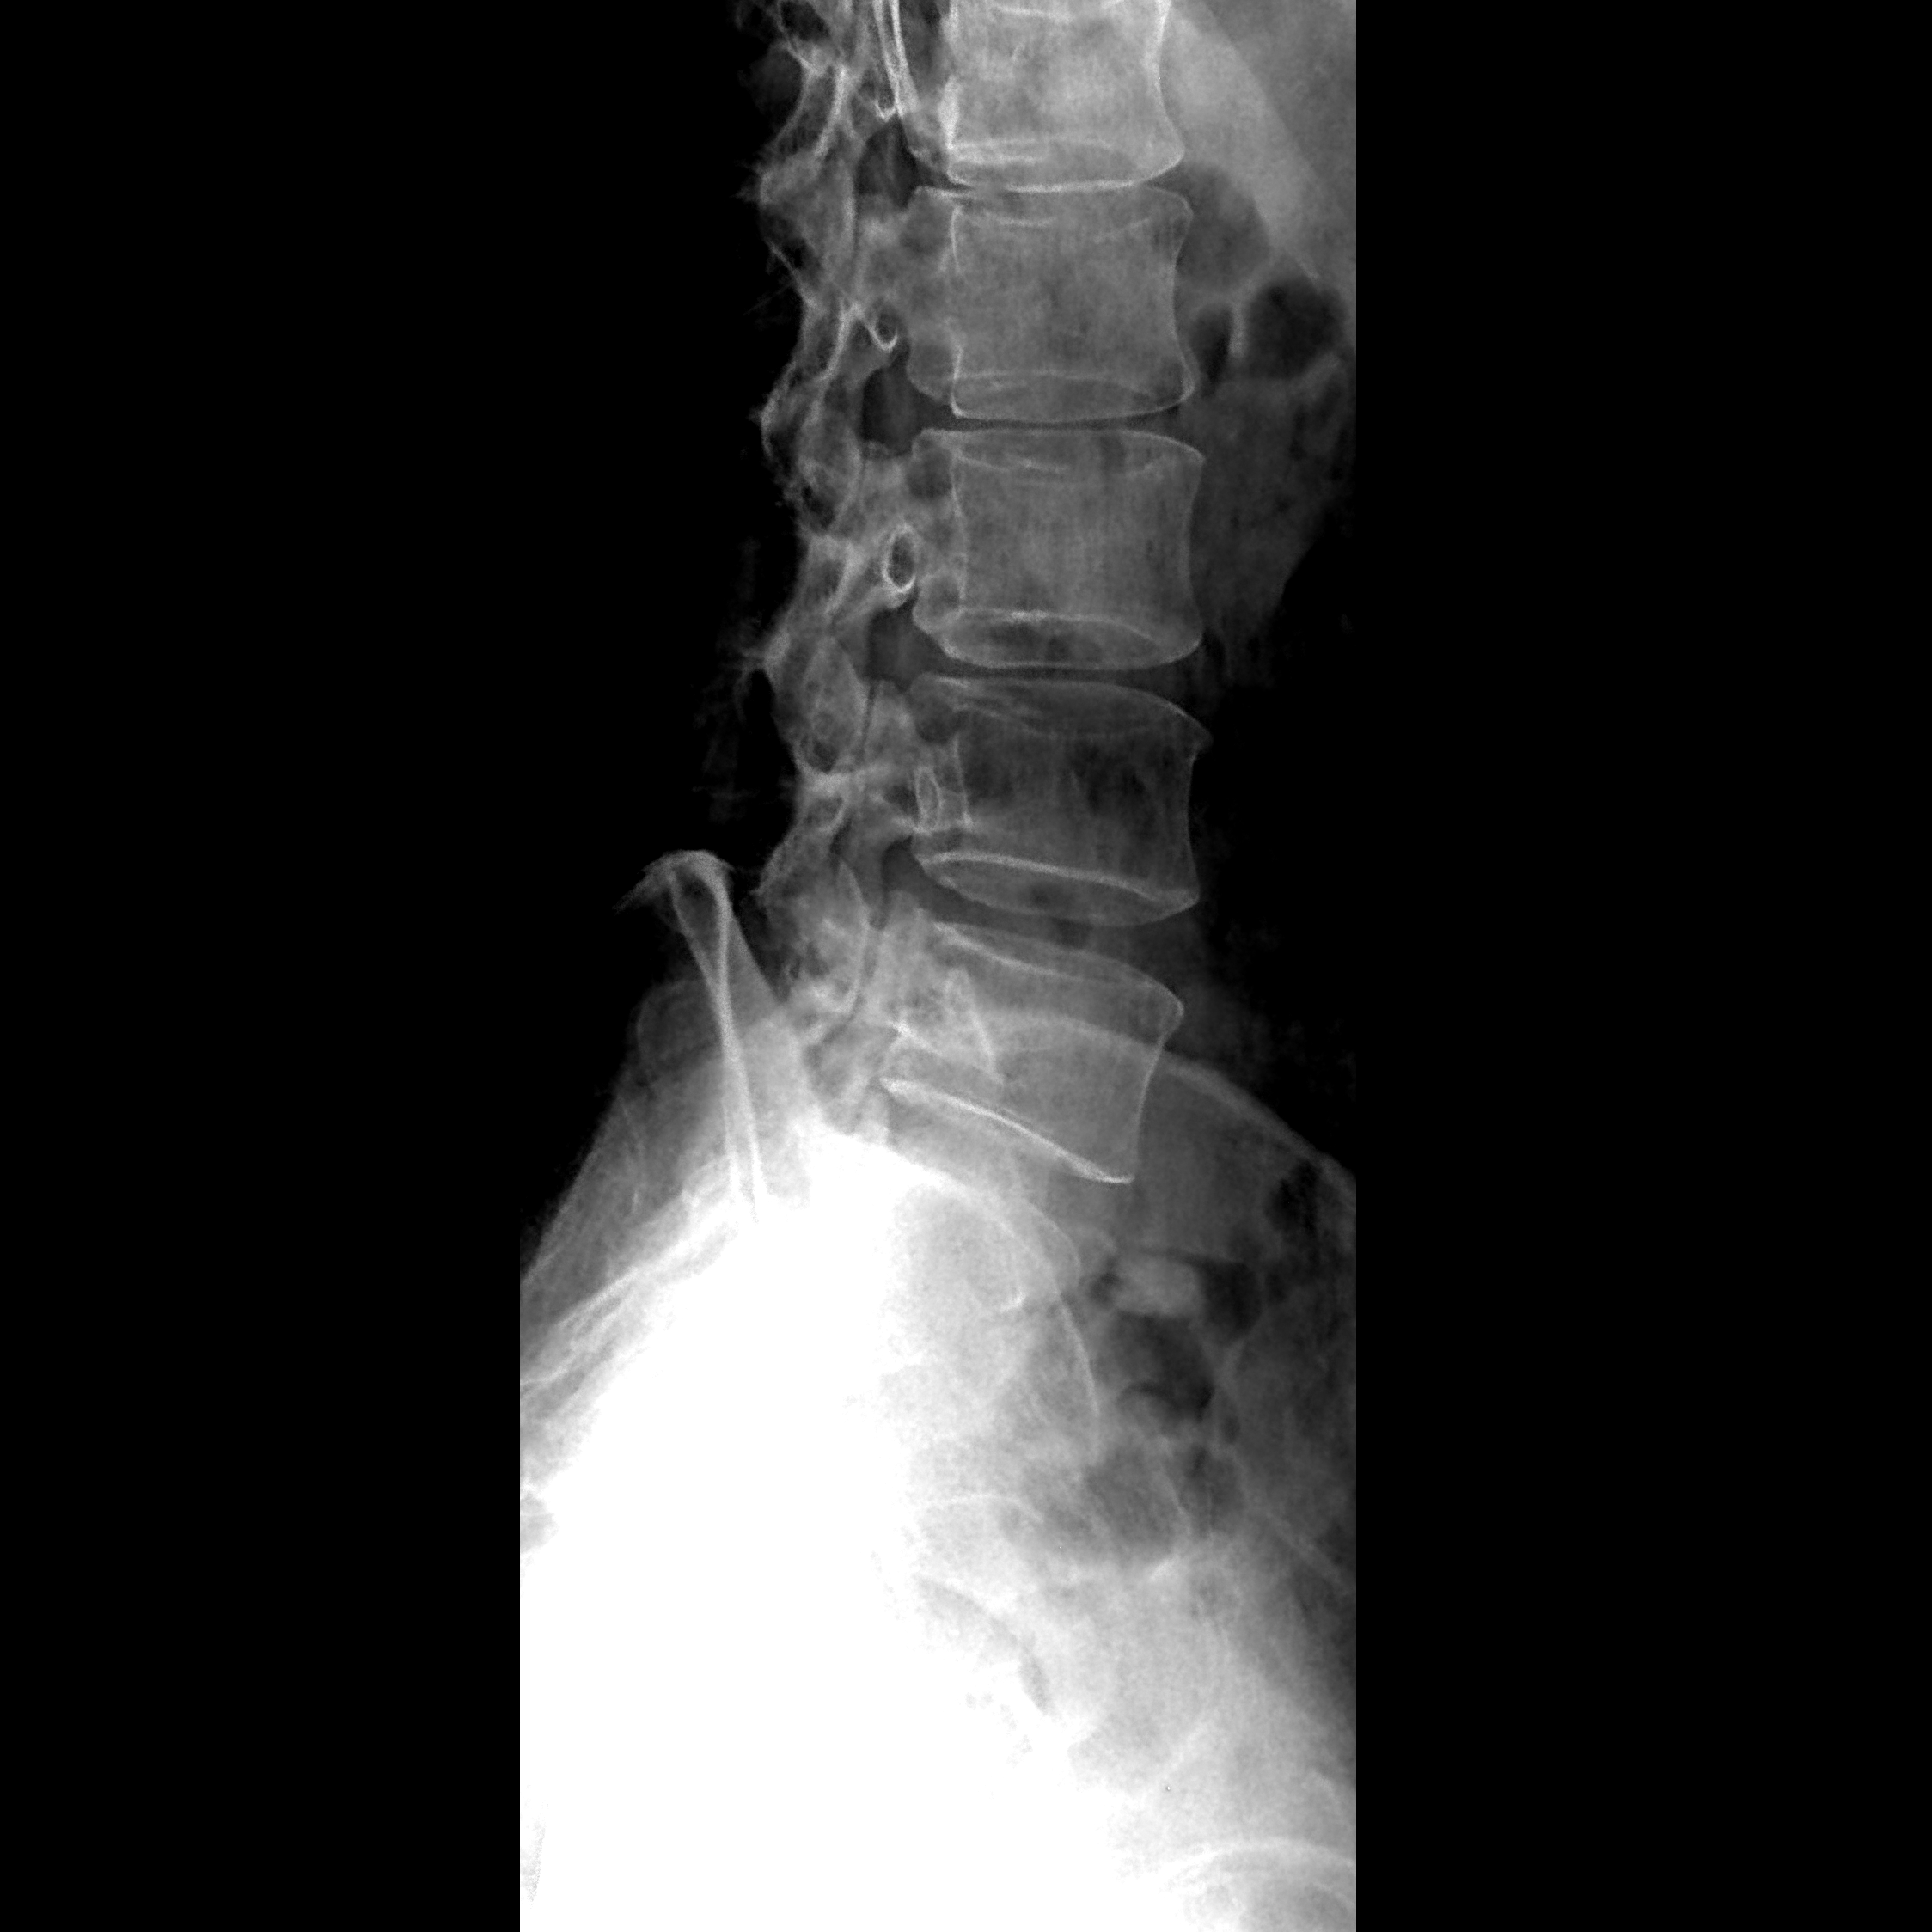

便携式X光机拍摄腰椎侧位